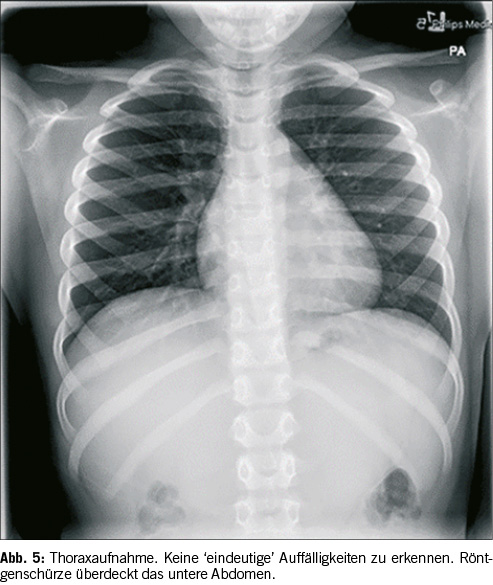

Eine weitere Erklärung für ein unauffindbares Objekt mag banal klingen, ist in der Praxis aber eine immer wieder auftretende Problematik: ein zu kleiner oder ungenügender Untersuchungsbereich. Oft kommt es vor, dass lediglich Aufnahmen des Thorax und des Pharynx gemacht werden. Das mag eventuell bei erst kürzlich ingestierten Fremdkörpern ausreichend sein, handelt es sich jedoch um eine Ingestion, welche einige Stunden oder sogar Tage zurückliegt [9], so befindet der Fremdkörper sich eventuell bereits im Abdomen. Auf Abbildung 5 ist kein deutlicher Fremdkörper zu finden. Die Erklärung dafür ist simpel. Der Fremdkörper ist bereits weiter distal im Magen-Darm-Trakt und auf der Thorax-Aufnahme nur von geübtem Auge knapp am unteren Bildrand zu erkennen. Zudem ist die Münze partiell von der Röntgenschürze abgedeckt. Verschiebt man die Abdeckung, welche über der Pelvis liegt, etwas nach unten, wie in Abbildung 5 geschehen, so wird eine Münze sichtbar. Dieser Fall illustriert eindeutig, dass bei Röntgenaufnahmen zur Lokalisierung von Fremdkörpern immer vom Rachen bis zum Anus untersucht werden sollte. Es ist dringend zu empfehlen eine Aufnahme des ganzen Thorax, des Pharynx, des Abdomenbereichs und der Pelvis zu machen. Eventuell ist auch noch eine seitliche Aufnahme des Thorax notwendig, um den Gegenstand zu erkennen. Ein Röntgenbild ist jedoch nicht bei jedem Gegenstand ausreichend. Bei auf Röntgenaufnahmen nicht erkennbaren Fremdkörpern, kann ein CT (Computed Tomography) aufschlussreich sein, da auf dem Querschnitt der zu untersuchenden Körperregion das Objekt besser erkannt werden kann.